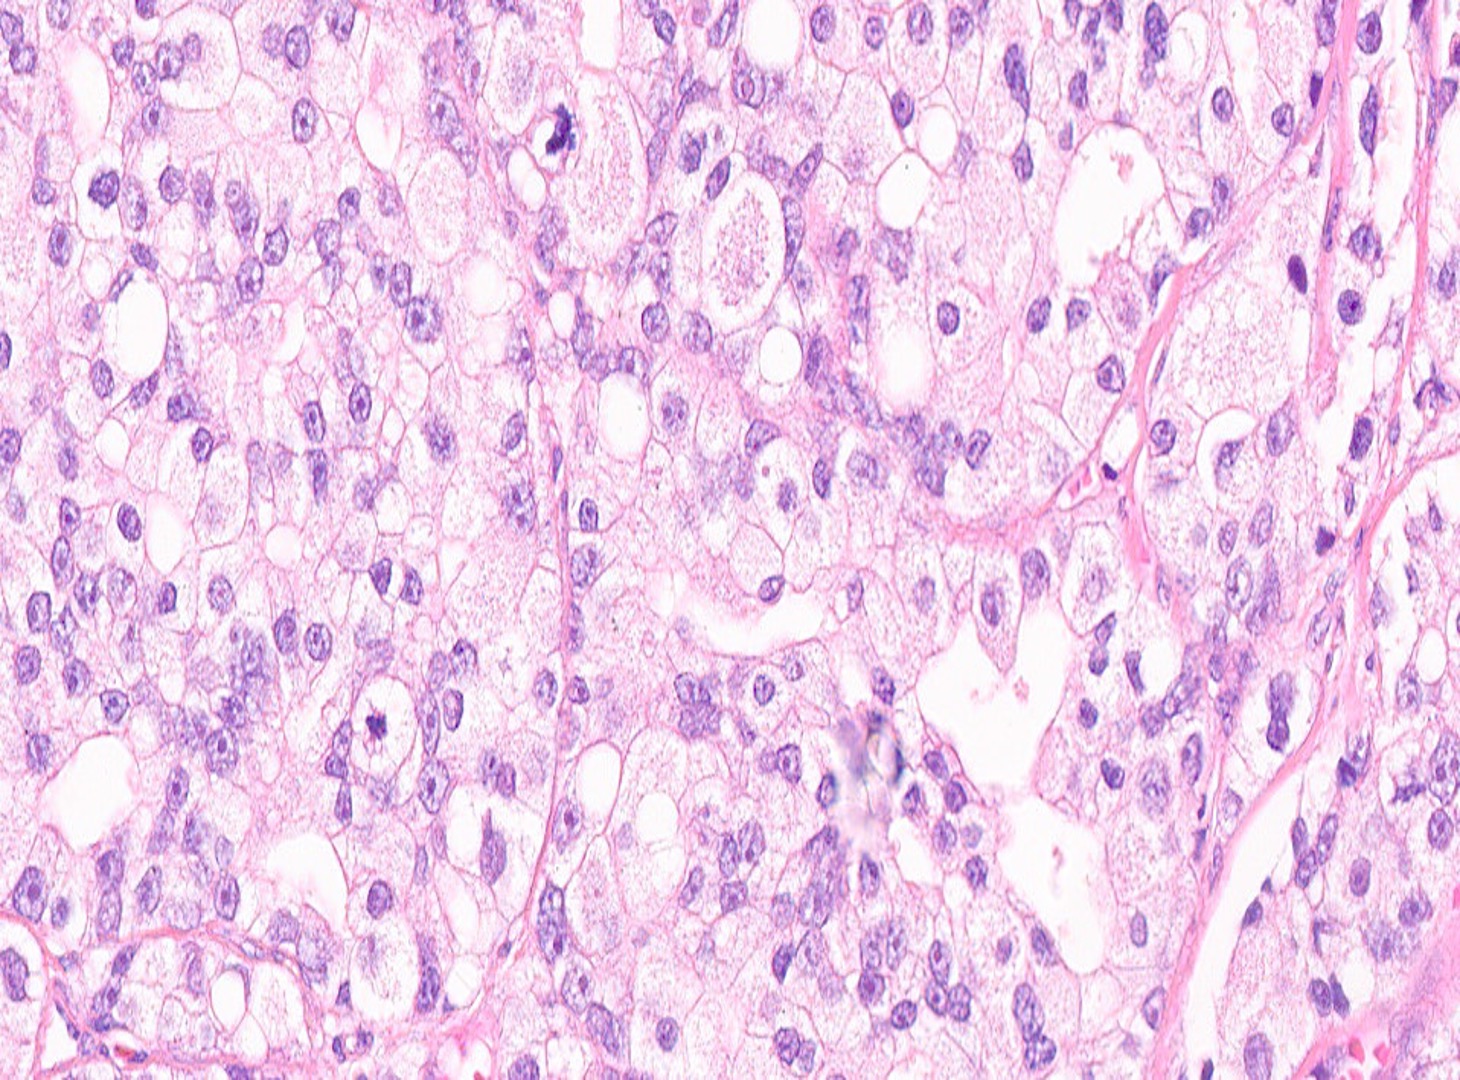

The patient is a 72-year-old male with a history of urinary hesitancy and nocturia, previously attributed to benign prostatic hyperplasia (BPH). He presented to his primary care physician with a 3-month history of unintentional weight loss (~12 lbs), fatigue, and right upper quadrant abdominal discomfort. No history of jaundice, hepatomegaly on exam, or alcohol use disorder. A CT abdomen/pelvis with contrast revealed multiple hypodense lesions in both hepatic lobes, the largest measuring 3.1 cm in segment VI, concerning for metastatic disease. The prostate was enlarged, but no discrete mass was identified on imaging. Bone scan showed sclerotic lesions in the pelvis and lumbar spine, consistent with osseous metastases. A liver biopsy was obtained from the largest lesion in the right hepatic lobe for diagnostic confirmation.

What is the diagnosis?

GU Pathology